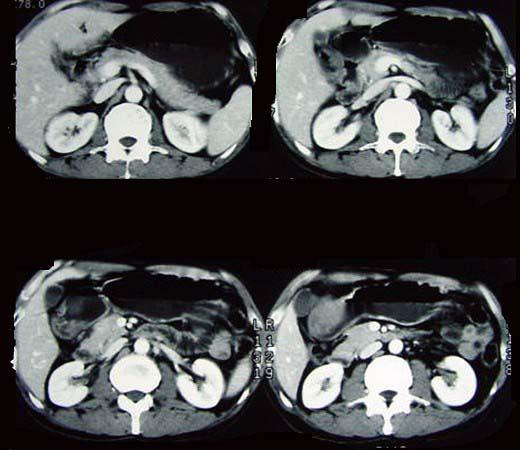

问题 女性,42岁,腹痛、黑便1周,CT扫描见胃窦部圆形块影,最佳的诊断是 ( )

选项 A.胃窦平滑肌瘤 B.胃癌 C.胃淋巴瘤 D.胃窦神经纤维瘤 E.胃内异物

答案 D